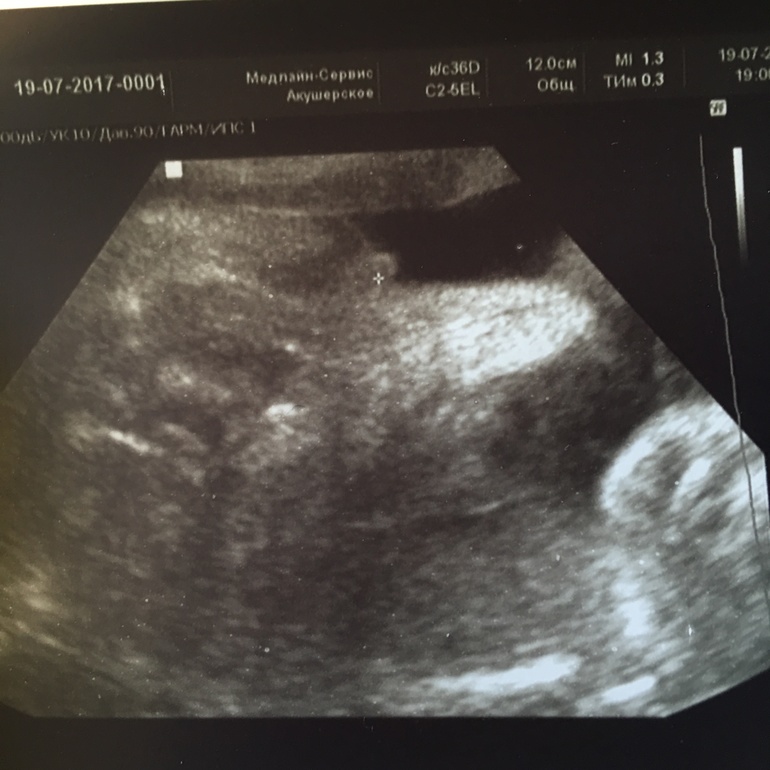

УЗИ в 30 недель

ДругоеСегодня на УЗИ сказали похоже девочка. А вы что скажете? Разве похоже на девочку? Крестиком отметил узист то самое.

ну как сказать,у меня подружке не могли пол определить,то отвернется,то пуповина между ног,то ручка,в общем ждали девочку)))а увидели в 30 с лишним,случайно,когда она смотрела шов от кс...и ей на тот момент сказали,что чем больше срок,тем сложнее увидеть,так как группируется плод и сжимается